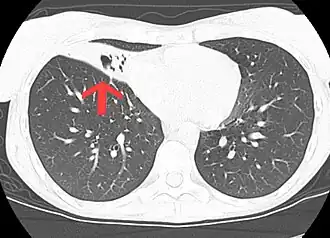

CT scan de múltiplos nódulos e bronquiectasia nos lóbulos médios pulmonares